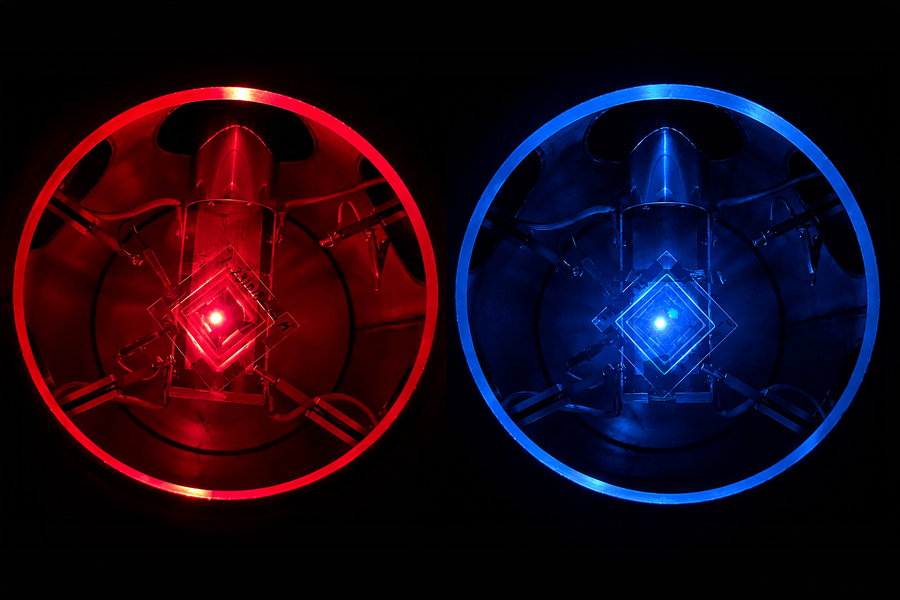

Researchers at MIT are developing a new kind of sensor that detects cancer-related signals inside the bladder and emits a fluorescent light to reveal their presence. By using these nanosensors to map bladder cancer biomarkers in real time, this approach could transform how we monitor and diagnose the disease.